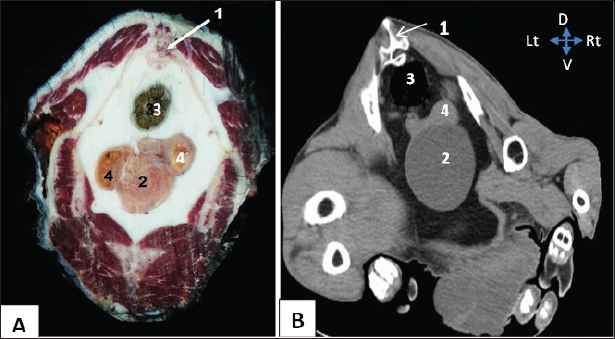

The egress of the left ureter from the left renal hilus was observed in the transverse CT image (Fig. 2). On transverse- and dorsal-plane CT scans (Figs. 3, 4), the urinary bladder may be identified at the sacrum level on the pelvic floor, located beneath the uterus and rectum. A dorsal-plane CT scan revealed the presence of the urethra exiting the urine bladder in a caudal direction (Fig. 4).

Fig. 3. Representative macrographic image of cross-sectional anatomy (Panel A) and computed tomography image (5-mm thickness) (Panel B) of the goat pelvis. Panel (A –B): 1- Sacrum; 2-Urinary bladder; 3- Rectum; 4-Uterus.